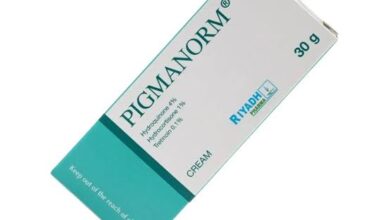

تجربتي مع كريم بيجمانورم

من خلال تجربتي مع كريم بيجمانورم الشهير، يمكن اعتباره واحدًا من أفضل الكريمات المفيدة في علاج العديد من مشكلات الجلد…